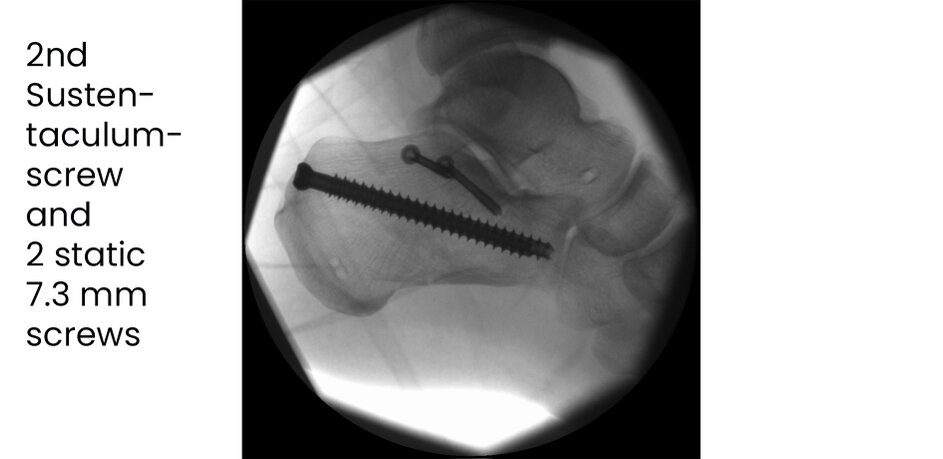

Case 17KL, male, 35y, surgery on day of trauma